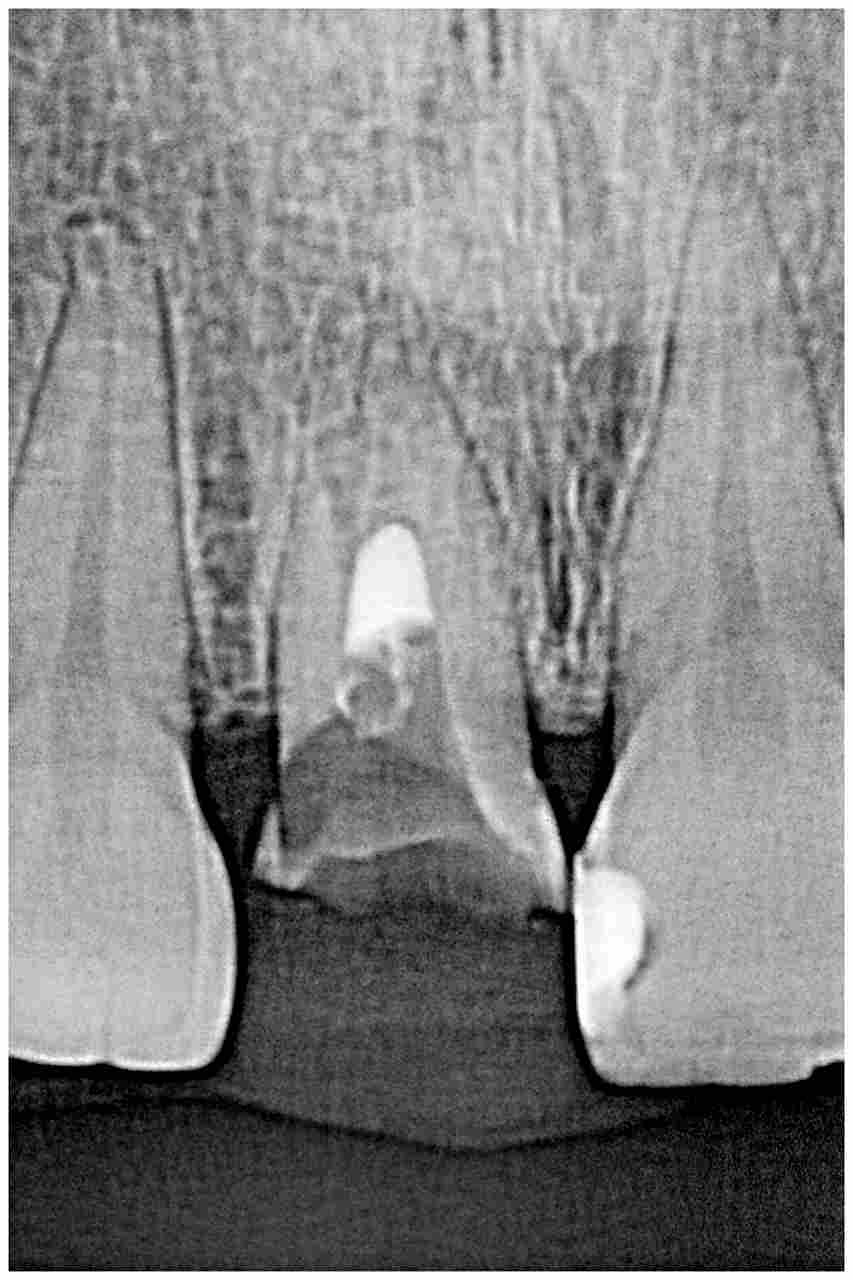

術前の口腔内になります

仮歯を外しました

口蓋側が歯が無くなっていました

外傷の既往がありそのため口蓋側の歯質が無くなっていました

確かに抜歯の歯だと思いました

術前の審査になります